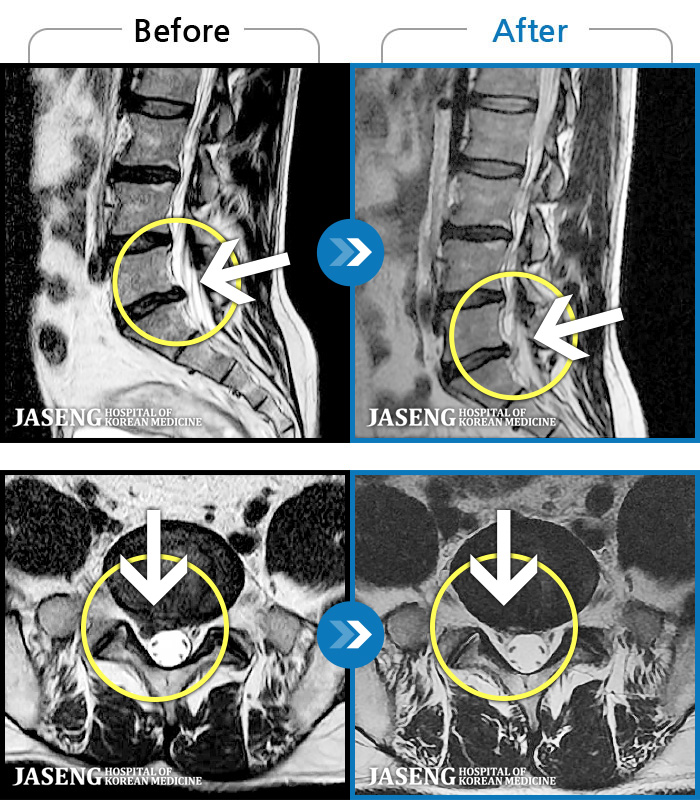

ȯںп Ǹ ǿ ԿǾ, ο ġ ۿ Ƿ ġḦ Ͻñ ٶϴ.